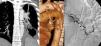

Presentamos el caso de un paciente de 31 años con antecedentes personales de una infección avanzada por VIH (estadio C3) con mal control terapéutico, que consultó por hemoptisis. En la radiografía de tórax se observaban secuelas de una infección pulmonar por tuberculosis que afectaban especialmente al hemitórax izquierdo. Una angio-TC de tórax identificó una fístula entre ramas tortuosas y dilatadas de la arteria bronquial izquierda, y una rama segmentaria filiforme de la arteria pulmonar lobar inferior izquierda (fig. 1A y B). Una arteriografía confirmó la existencia de dicha fístula (fig. 1C), procediéndose a su embolización.

A) Reconstrucción MIP (proyección de intensidad máxima) coronal de TC en la que se identifica una comunicación entre ramas tortuosas de la arteria bronquial izquierda (flechas negras) y una rama segmentaria filiforme (flechas blancas) de la arteria del lóbulo inferior izquierdo. Nótense las secuelas por tuberculosis del hemitórax izquierdo. B) Reconstrucción 3D (volume rendering) de TC de tórax (Ao: aorta; P: arteria pulmonar) en la que se aprecia mejor la fístula entre ramas de la arteria bronquial izquierda (flechas negras) y la arteria pulmonar (flechas blancas). C) Arteriografía en la que se visualiza el llenado retrógrado de las arterias pulmonares (flechas blancas) desde las ramas tortuosas de la arteria bronquial izquierda (flechas negras).